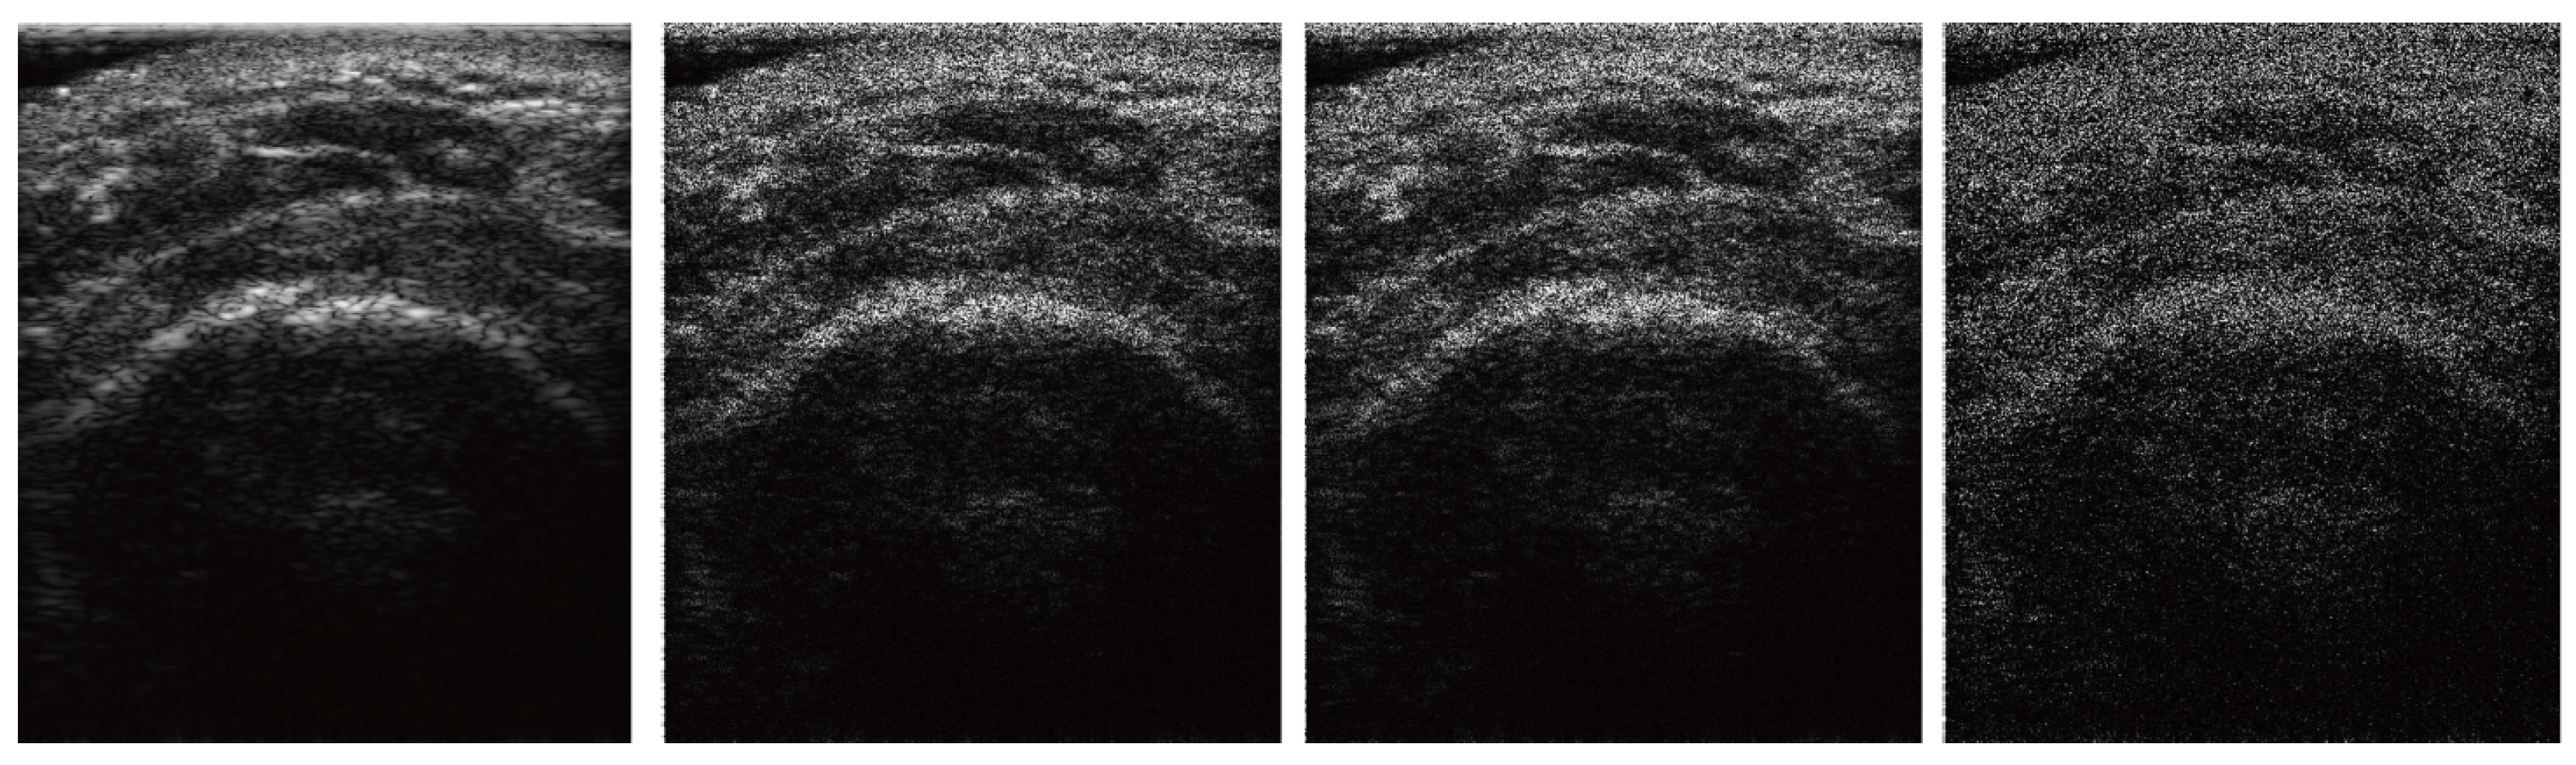

To examine how SMART-CA is robust to the noise of US images, SMART-CA performance in segmenting an RCT was compared under different speckle noise levels of the US images. Randomly generated speckle [33] noises were added to the original US images. Figure 5 shows example images with different levels of speckle noises.

Figure 5.

The images at different speckle noise level. Each column indicates original, 15 db, 12 db, and 10 db images.